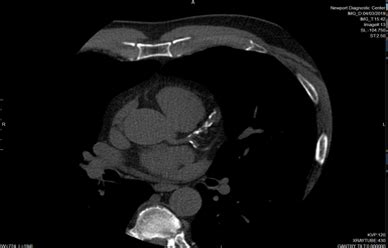

When we talk about Newport Beach imaging , one of the first things that should come to mind is the state-of-the-art technology these facilities are packing. Seriously, guys, the advancements in medical imaging are mind-blowing! We’re not just talking about basic X-rays anymore (though those are still super important!). Modern imaging centers in Newport Beach are equipped with the latest generation of MRI machines, CT scanners, ultrasound devices, and digital mammography systems. What does this mean for you? It means clearer images , faster scan times , and often, reduced radiation exposure . For instance, newer MRI machines are wider and quieter, making the experience less claustrophobic and more comfortable for patients. They can capture incredibly detailed images of soft tissues, making diagnoses for conditions affecting the brain, joints, and internal organs much more precise. Similarly, advancements in CT technology allow for incredible 3D reconstructions of the body, helping doctors visualize complex structures and plan surgeries with unparalleled accuracy. Advanced diagnostic imaging in Newport Beach isn’t just a buzzword; it’s a reality that directly impacts the quality of care you receive. These technologies enable early detection of diseases , which is, let’s be honest, crucial . Catching something early often means simpler treatment options and better outcomes. So, when you’re looking into imaging services in Newport Beach , ask about the technology they use. It’s a strong indicator of their commitment to providing you with the best possible diagnostic information . Investing in the latest tech is an investment in your health, plain and simple. The goal is always to provide physicians with the most comprehensive data so they can make the most informed decisions about your care. This focus on technology ensures that patients in Newport Beach have access to world-class diagnostic capabilities, right in their backyard.

What’s really awesome about the imaging centers in Newport Beach is the sheer breadth of services they offer. It’s not a one-size-fits-all situation, guys. Whether you need a simple screening or a highly specialized diagnostic procedure, you’ll find it here. Let’s break down some of the key services you can expect. Diagnostic imaging Newport Beach covers everything from routine screenings to intricate problem-solving. Think about MRI (Magnetic Resonance Imaging) , which uses powerful magnets and radio waves to create detailed images of organs, soft tissues, bone, and virtually all other internal body structures. It’s fantastic for evaluating injuries, neurological conditions, and cancer. Then there’s CT (Computed Tomography) scanning , which uses X-rays to create cross-sectional images of the body. It’s super useful for examining bones, detecting tumors, and looking at internal injuries quickly. Ultrasound is another big one – it uses sound waves to create images and is a go-to for examining abdominal organs, the heart, blood vessels, and during pregnancy. It’s non-invasive and incredibly safe. For women, mammography is vital for breast cancer screening, and modern digital mammography offers higher accuracy and lower radiation doses. Beyond these core services, many centers also offer specialized imaging like DEXA scans for bone density, fluoroscopy for real-time X-ray imaging (think watching contrast agents move through your digestive system), and interventional radiology , where minimally invasive procedures are guided by imaging. The diversity of imaging services in Newport Beach means you can often get multiple types of scans at a single, convenient location. This saves you time and hassle, and ensures continuity of care. When you’re researching Newport Beach imaging facilities , consider the full range of services they provide. Do they offer the specific type of scan you need? Are there specialized services that might be beneficial for your health concerns? Having a comprehensive suite of options available locally makes a huge difference in managing your health proactively. It’s about having access to the right tools at the right time, all within your community. This comprehensive approach ensures that whether it’s a common ailment or a rare condition, the imaging capabilities in Newport Beach are robust enough to provide answers.